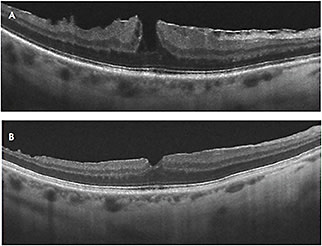

On OCT, a LMH has the following characteristics1,2:

• An irregular inner foveal contour;

• A defect in the inner retina layers of the fovea;

• Intraretinal splitting (schisis) between inner and outer retina;

• Intact photoreceptors; and

• Usually epiretinal membrane or thickened residual posterior hyaloid (Figure 1).

Figure 1. Lamellar macular hole associated with ERM. Note the loss of inner retinal tissue, schisis, and intact photoreceptors.